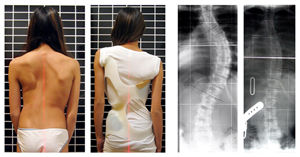

特發(fā)性脊柱側(cè)彎

特發(fā)性脊柱側(cè)凸是脊柱的側(cè)偏畸形,原因不明。因為還有脊椎旋轉(zhuǎn)而不僅僅是偏離,所以術(shù)語脊柱側(cè)彎也被用來描述畸形。

青少年特發(fā)性脊柱側(cè)彎的特征是脊柱三維畸形伴有側(cè)彎加椎體旋轉(zhuǎn)。

身體檢查涉及姿勢和身體輪廓的基線評估。

注意雙肩是否不平,是否有肩胛骨突出。

當后肋骨在曲線的凸側(cè)向后推動時,可能會出現(xiàn)肋骨隆起。

此外,肋在凹側(cè)緊密靠近,在凸側(cè)分開。

特發(fā)性脊柱側(cè)彎有四種模式

胸廓曲線

腰椎曲線

同側(cè)胸腰椎曲線

相對兩側(cè)的胸椎和腰椎曲線